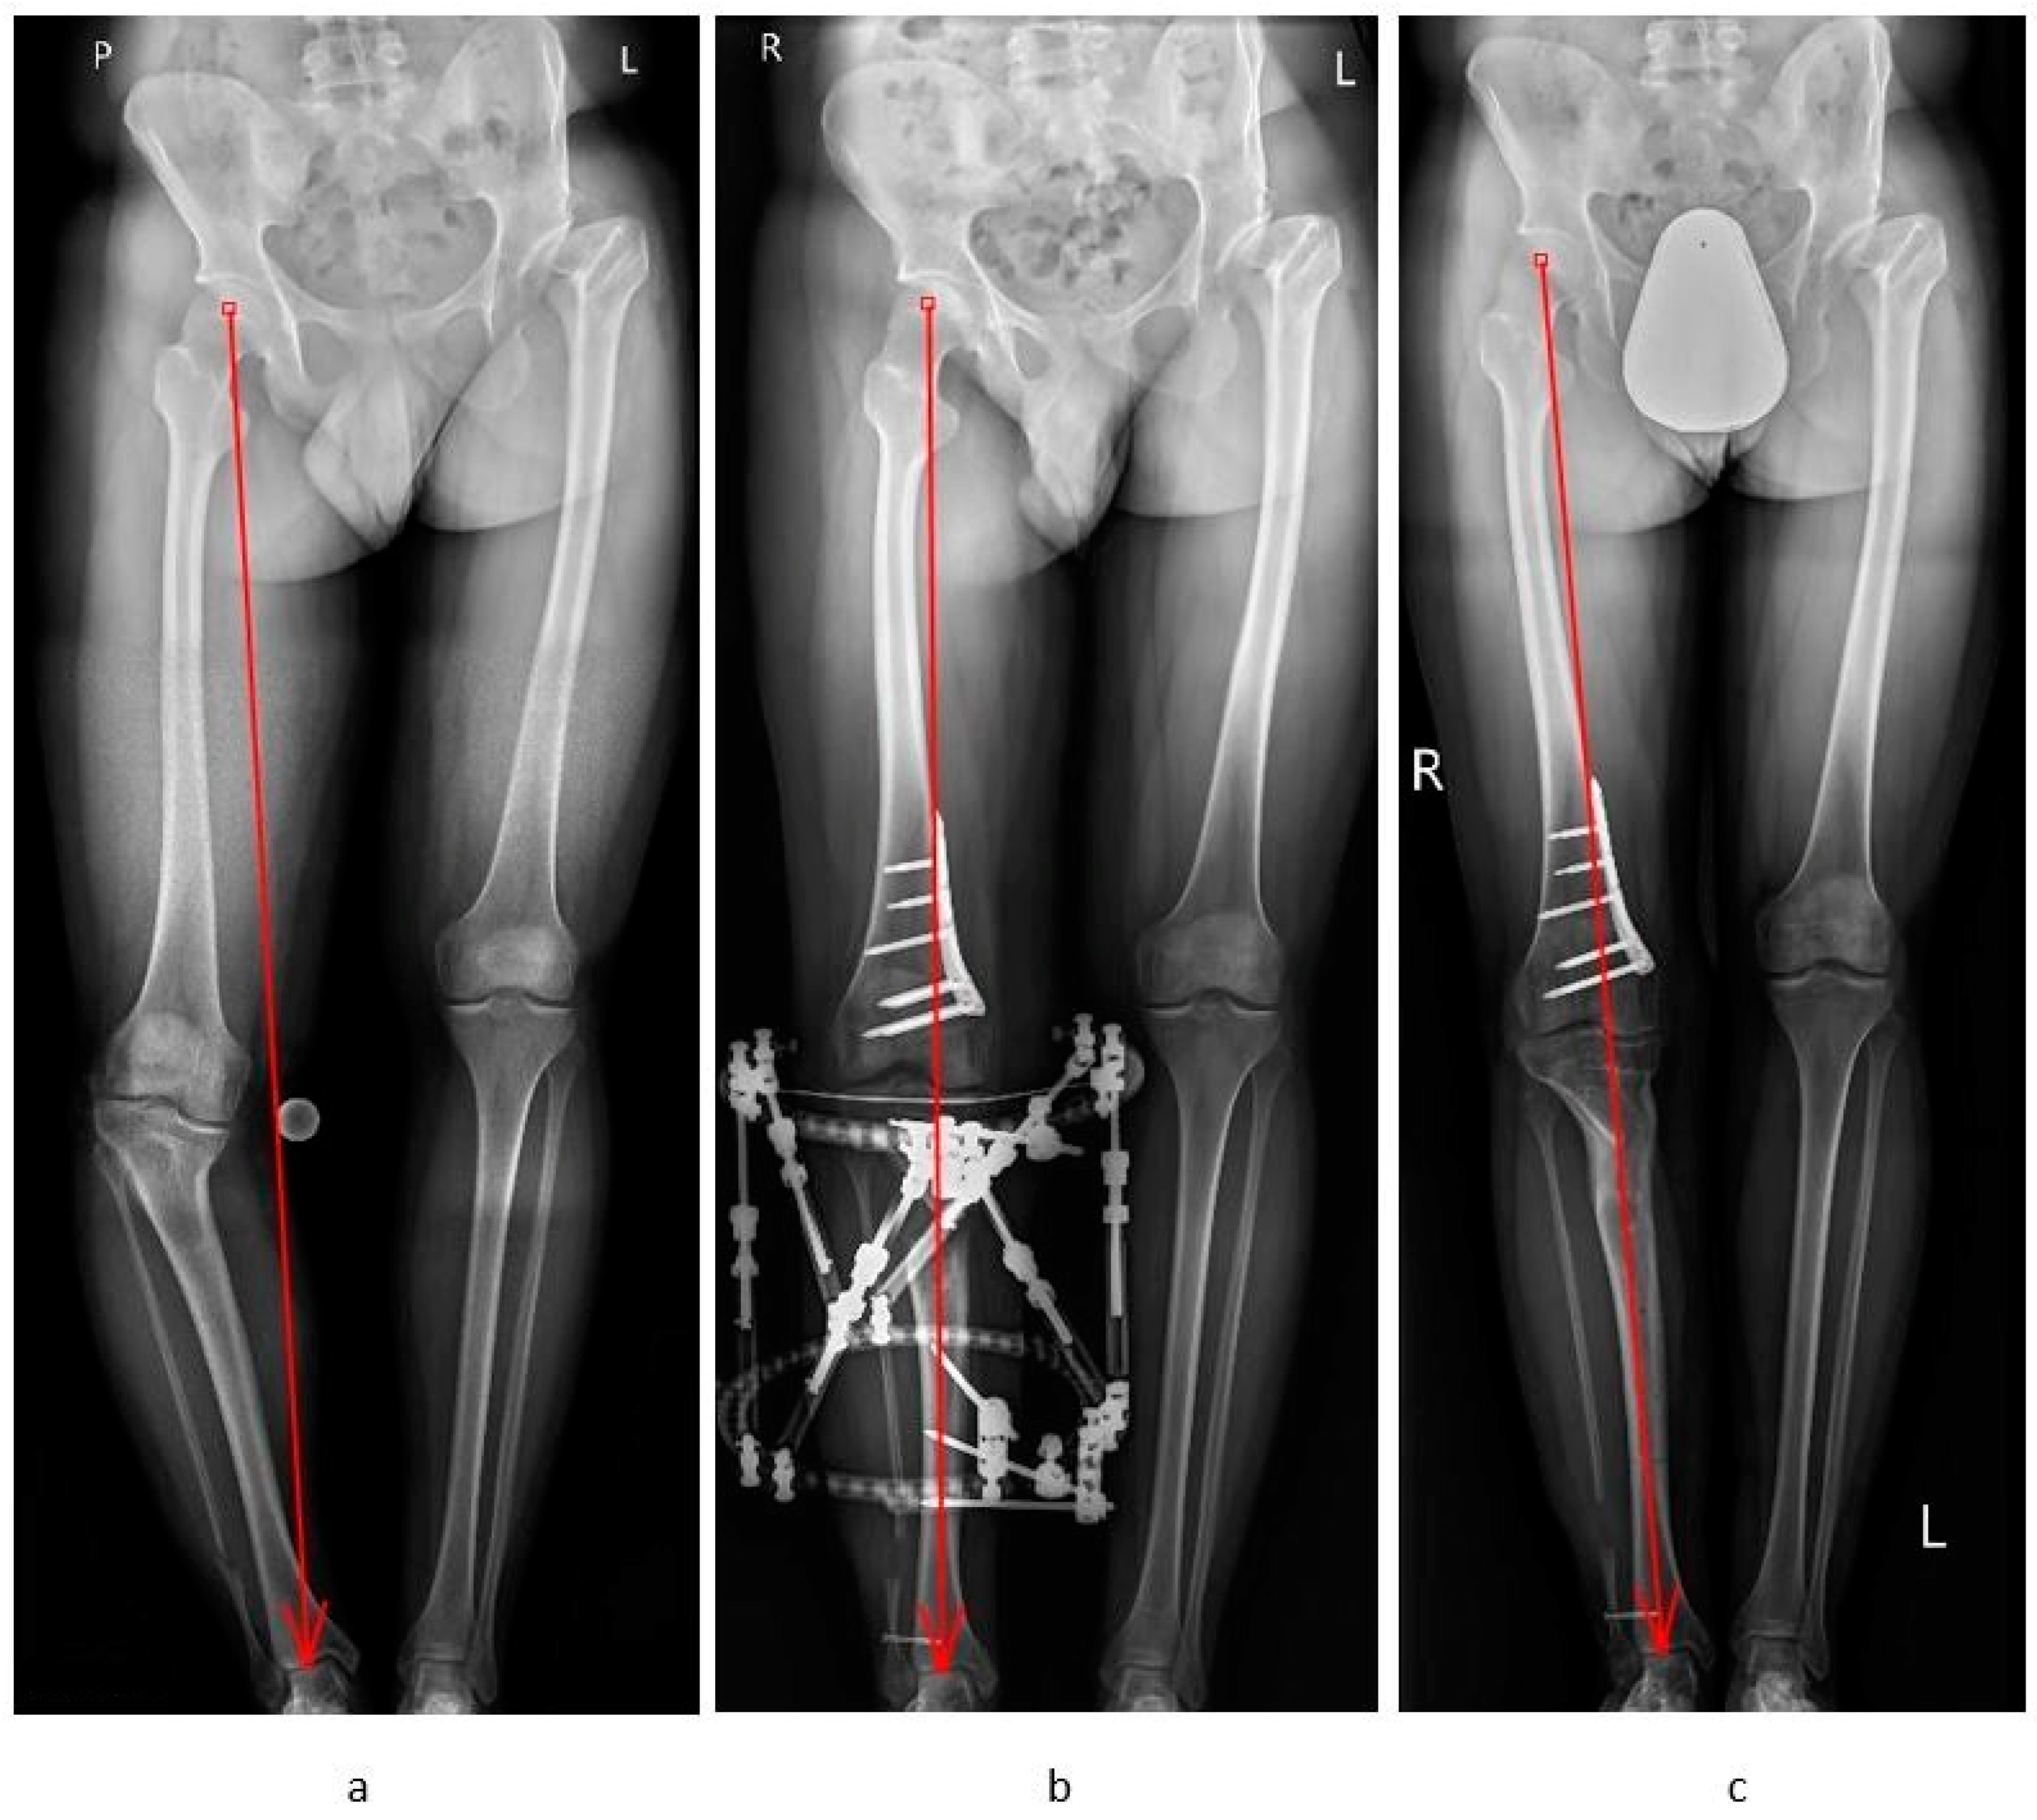

HOT ! Knee Osteotomy アップデート Corrective Osteotomies in Severe Non-Idiopathic Lower Limb

Knee Osteotomy アップデート Corrective Osteotomies in Severe Non-Idiopathic Lower Limbの詳細情報

Corrective Osteotomies in Severe Non-Idiopathic Lower Limb。Arthrex - Plate, Tibial A/P Sloped Osteotomy, 7.5 mm - AR。Distal Tibial Tuberosity Arc Osteotomy in Open-Wedge。膝の骨切り術に関する最新情報を提供する専門書。専用 SURGEON 110, 111, 157 3冊セット。AR-13200T-17.5.jpg。裁断済みです。定価12000

• Corrective Osteotomies in Severe Non-Idiopathic Lower Limb

• Distal Tibial Tuberosity Arc Osteotomy in Open-Wedge